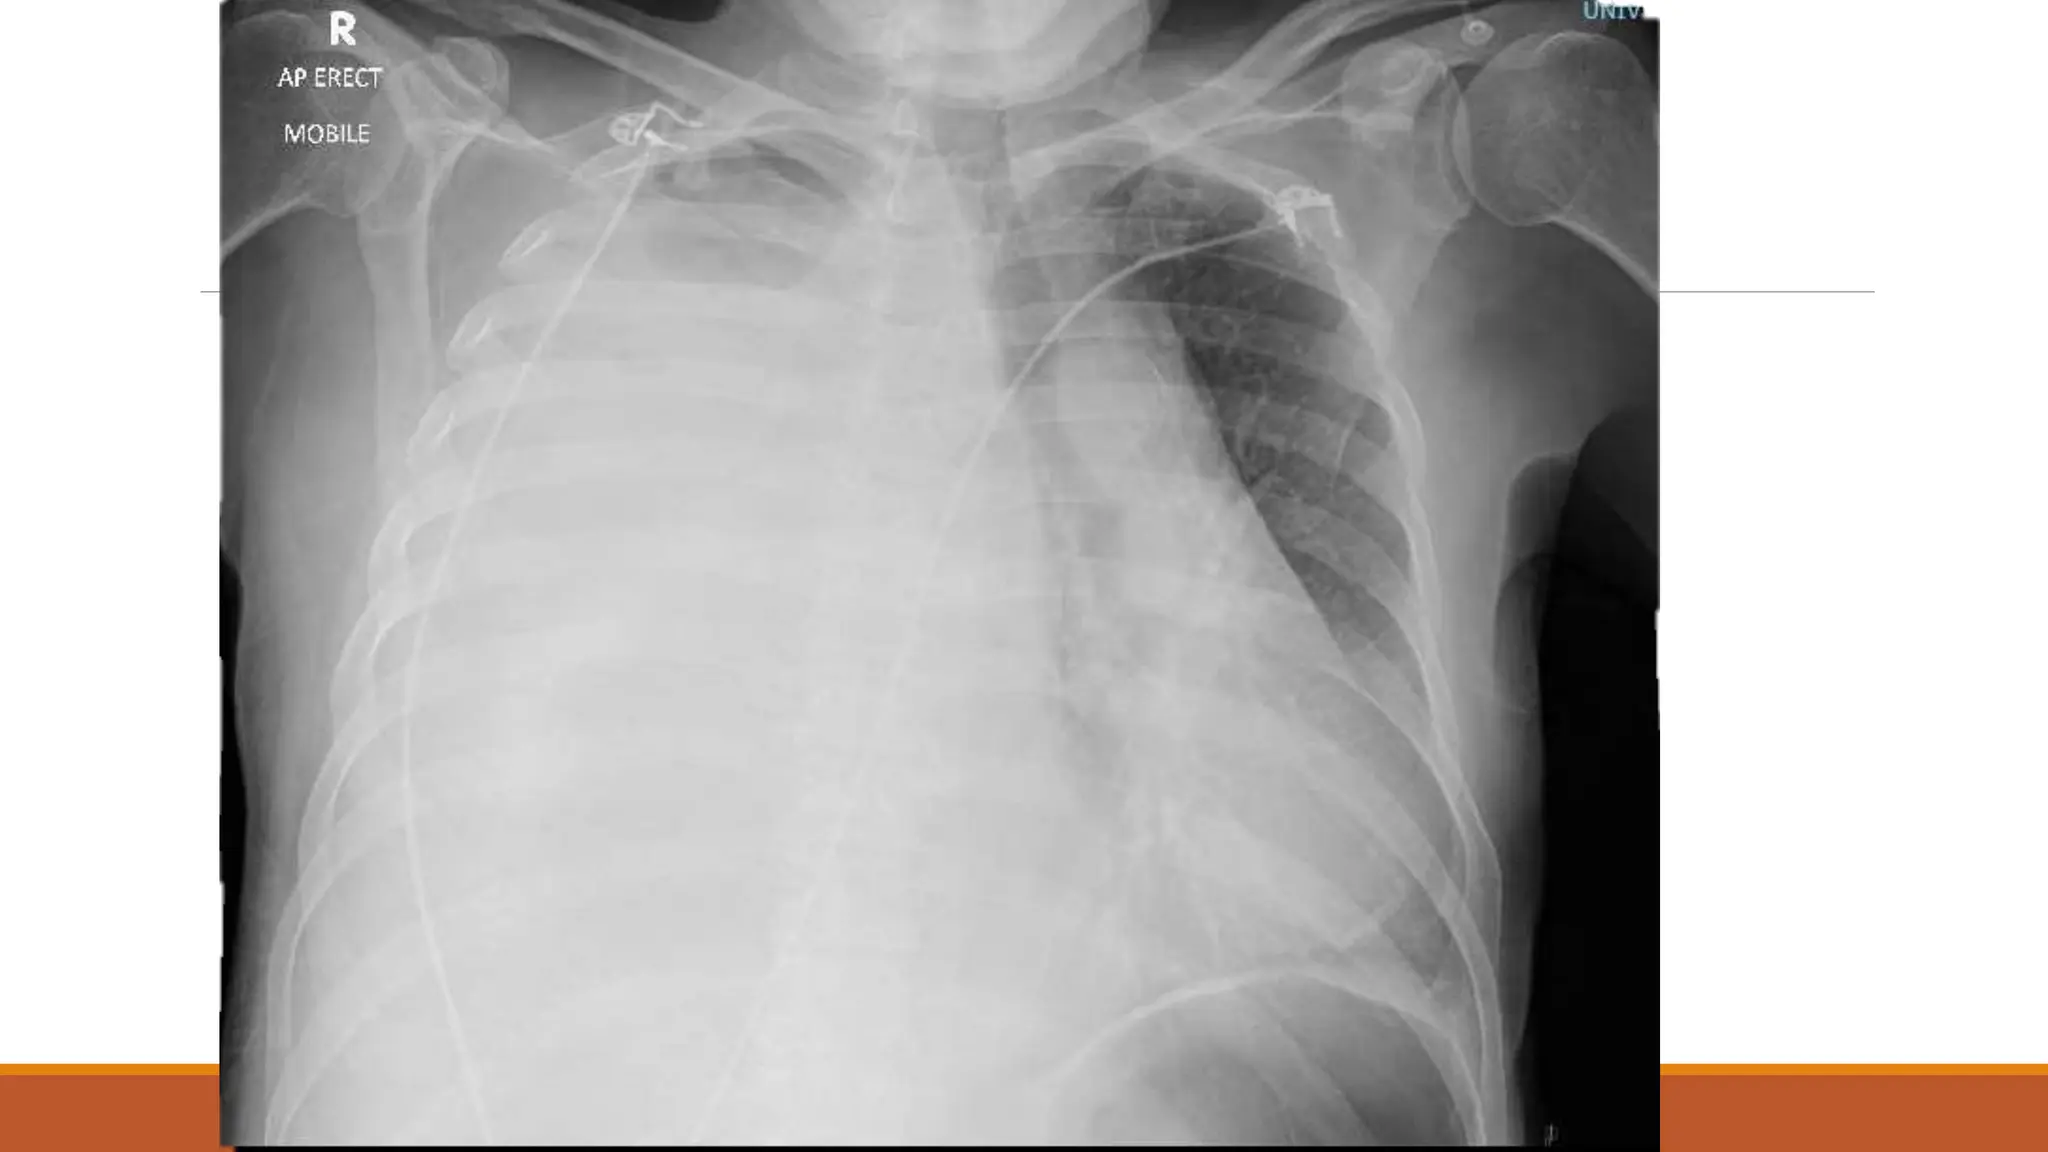

63 male

Normally F&W, no regular medications

Became unwell 7th Dec 2020 – cough, yellow sputum

Saw GP 23rd Dec – oral doxy

No real improvement – Clarithromycin 6/1/21

Again no improvement

Progressive loss of appetite and weight over a couple of months – given fortisip, which stopped

weight loss, but poor appetite continued

Progressive right shoulder pain and inability to lie on left side due to dyspnoea

On examination

OE: Acutely distressed, in significant pain and sats dropped to 80% when sat forwards, but 98%

when reclined at 60 degrees

Chest – no air entry right side